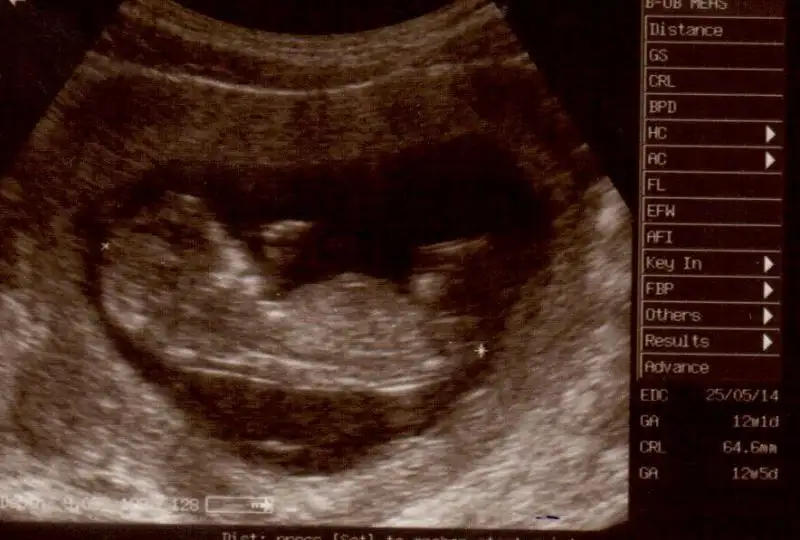

canım bıde buna bakarmısın nolur 12 + 5 Eki Görüntüle 857255 Eki Görüntüle 857256